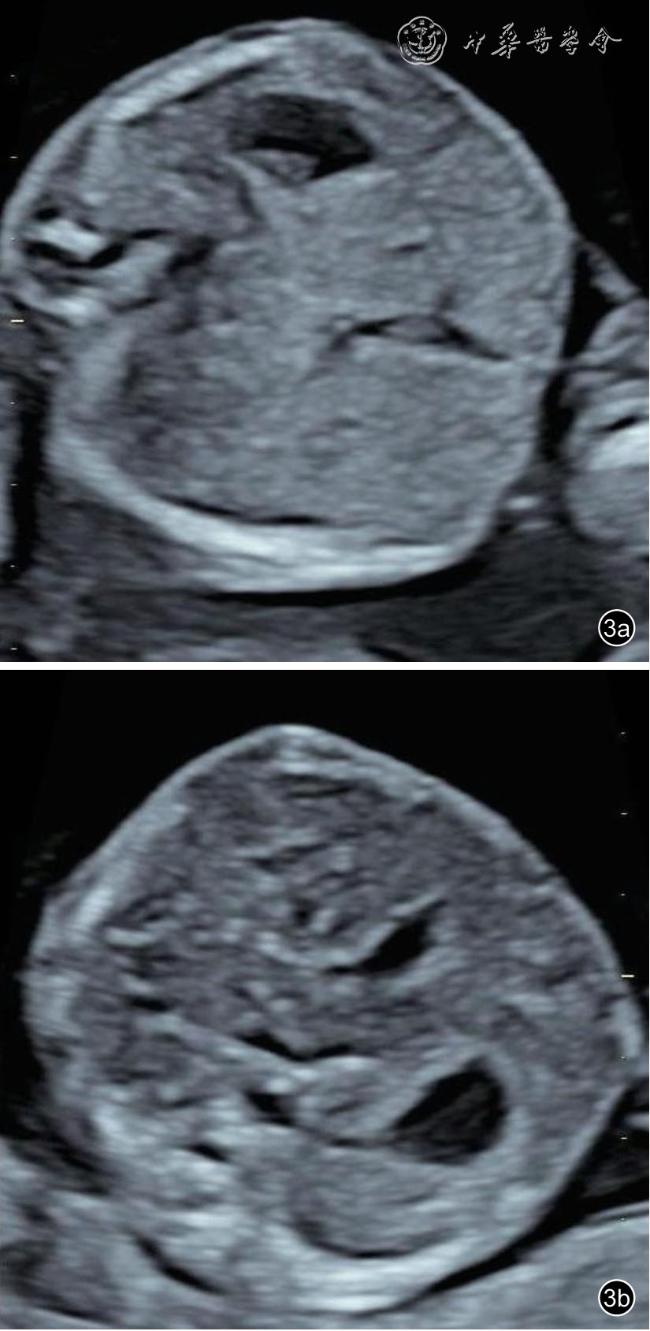

26 例TAPS 均在中晚孕期(孕17+1~34+6 周)超声检查中发现,其中Ⅰ期11 例,Ⅱ期3 例,Ⅲ期3 例,Ⅳ期9 例,Ⅴ期0 例。共有的超声特征为:(1)供血儿MCA-PSV 增高(>1.5 MoM),受血儿MCA-PSV 降低(<1.0 MoM)( 图1);(2)“黑白”胎盘:供血儿脐带入口附近胎盘回声增强、增厚,受血儿脐带入口附近胎盘回声减低、较供血儿侧薄(图2)。其他超声特征包括:(1)24例(92%)受血儿肝呈“星空征”(图3);(2)4例(15%)供血儿肠管回声增强(图4);(3)22例(85%)心脏异常,包括心胸比增大、房室瓣反流、房室瓣频谱呈单峰、心肌增厚等征象(图5a、5b);(4)18 例(69%)多普勒血流异常,包括脐动脉、脐静脉、静脉导管A 波异常等;(5)9 例(34%)胎儿水肿,包括皮肤水肿、胸腹腔积液、心包积液;(6)15 例(57%)羊水量不均衡;(7)19 例(73%)脐带异常,包括脐带水肿、脐带插入点异常(图6);(8)15 例(57%)合并双胎选择性宫内生长受限(selective intrauterine growth restriction,sIUGR)、TTTS(表1)。对供血儿及受血儿其他超声特征进行统计分析发现,受血儿肝“星空征”、脐带水肿,供血儿肠道回声增强、胎儿水肿、心胸比增大特征比较,差异有统计学意义(P<0.05,表2)。

图4 双胎贫血-红细胞增多序列征胎儿孕22+5 周产前超声图像可见供血儿部分肠管肠壁回声增强(图a),略低于骨骼回声(Ⅰ级)(图b)